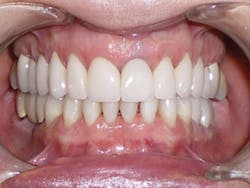

The six-week follow-up visits with Evin were eye-opening! I had the opportunity to observe his periodontal condition improve at each interval. After 30 aligners, or 15 short months, Evin's clear aligner orthodontic treatment was completed and final photos were taken. His bite was checked to confirm we had achieved our initial goal. Evin now had the appropriate overbite, overjet, and class I occlusion with proper posterior intercuspation with no interferences.

Figure 1

Retainers, similar to the aligners, but a medical grade heavier, were delivered to Evin and he was advised to wear them nightly.

Evin's treatment was completed in 2006. Fast forward nine years, and Evin schedules six-month preventive recare visits with our hygienist and still follows excellent home care. He has enjoyed nine years of health, comfort, and stability.